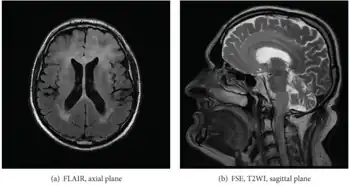

Axial fluid-attenuated inversion recovery MRI image demonstrating tumor-related infiltration involving both temporal lobes (Short arrow), and the substantia nigra (Long arrow).

a,b) Images of Gliomatosis cerebri.

Before the advent of MRI, diagnosis was generally not established until autopsy. Even with MRI, however, diagnosis is difficult.[8] Typically, gliomatosis cerebri appears as a diffuse, poorly circumscribed, infiltrating non-enhancing lesion that is hyperintense on T2-weighted images and expands the cerebral white matter. It is difficult to distinguish from highly infiltrative anaplastic astrocytoma or GBM.